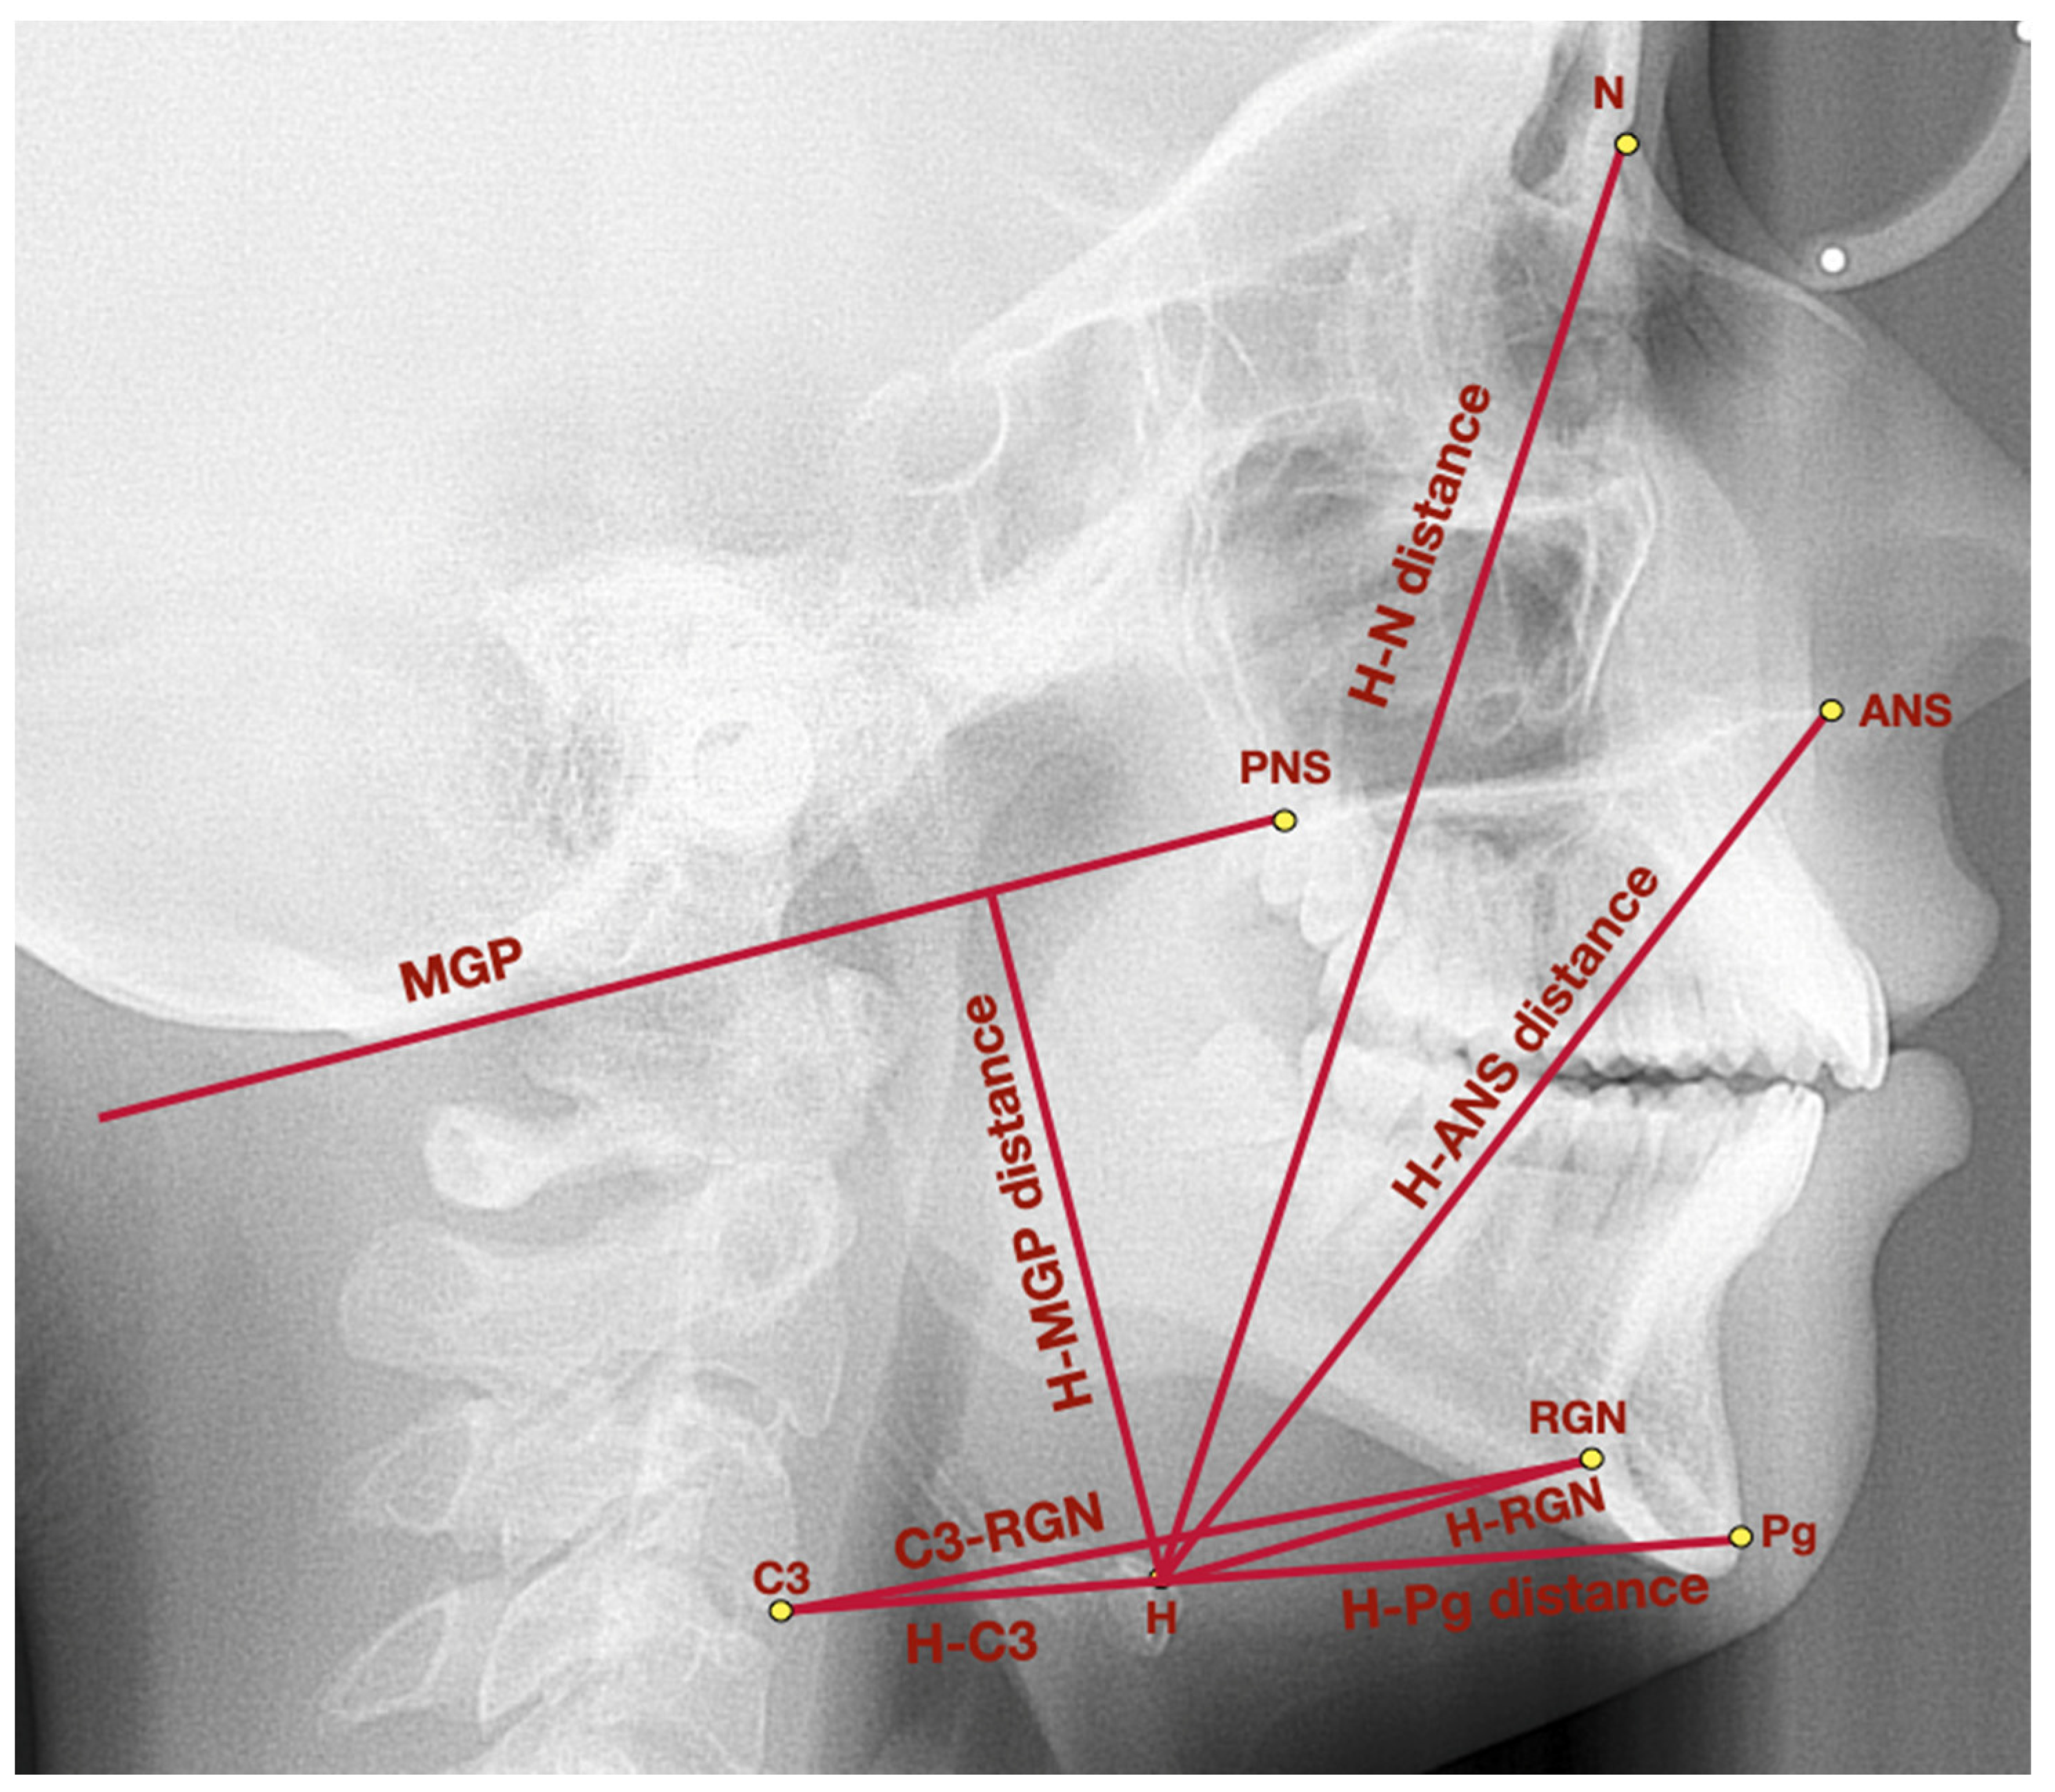

| Measurement | Point/Line/Angle | Description |

|---|---|---|

| General points and lines | Point ANS | Anterior nasal spine–the most prominent point of the anterior nasal spine |

| Point PNS | Posterior nasal spine–the most posterior point of hard palate, crossed by the pterygopalatine fossa | |

| Point Pg | Pogonion–the most prominent point localized in the mental tuberosity | |

| Point N | Nasion–the most anterior point localized in the frontonasal suture | |

| Point H | Hyoidale–the most superior anterior point of the body of the hyoid bone | |

| Point C3 | The most inferior anterior angle of the body of the third cervical vertebra | |

| RGN | Retrognathion–the most posterior inferior aspect of the mandibular symphysis | |

| MGP | McGregor’s Plane–line which links posterior nasal spine with the basiocciput | |

| Hyoid triangle | H-C3 distance | The distance between the points: H and C3 |

| H-RGN distance | The distance between the points: H and RGN | |

| C3-RGN distance | The distance between the points: C3 and RGN | |

| H-H’ distance | The height of the hyoid triangle, measured as a distance between point H and the perpendicular projection of point H onto C3-RGN line | |

| Hyoid bone topography | H-MGP distance | The distance measured between point H and the perpendicular projection of point H onto MGP |

| H-N distance | The distance between the points: hyoidale and nasion | |

| H-ANS distance | The distance between the points: hyoidale and anterior nasal spine | |

| H-Pg distance | The distance between the points: hyoidale and pogonion | |